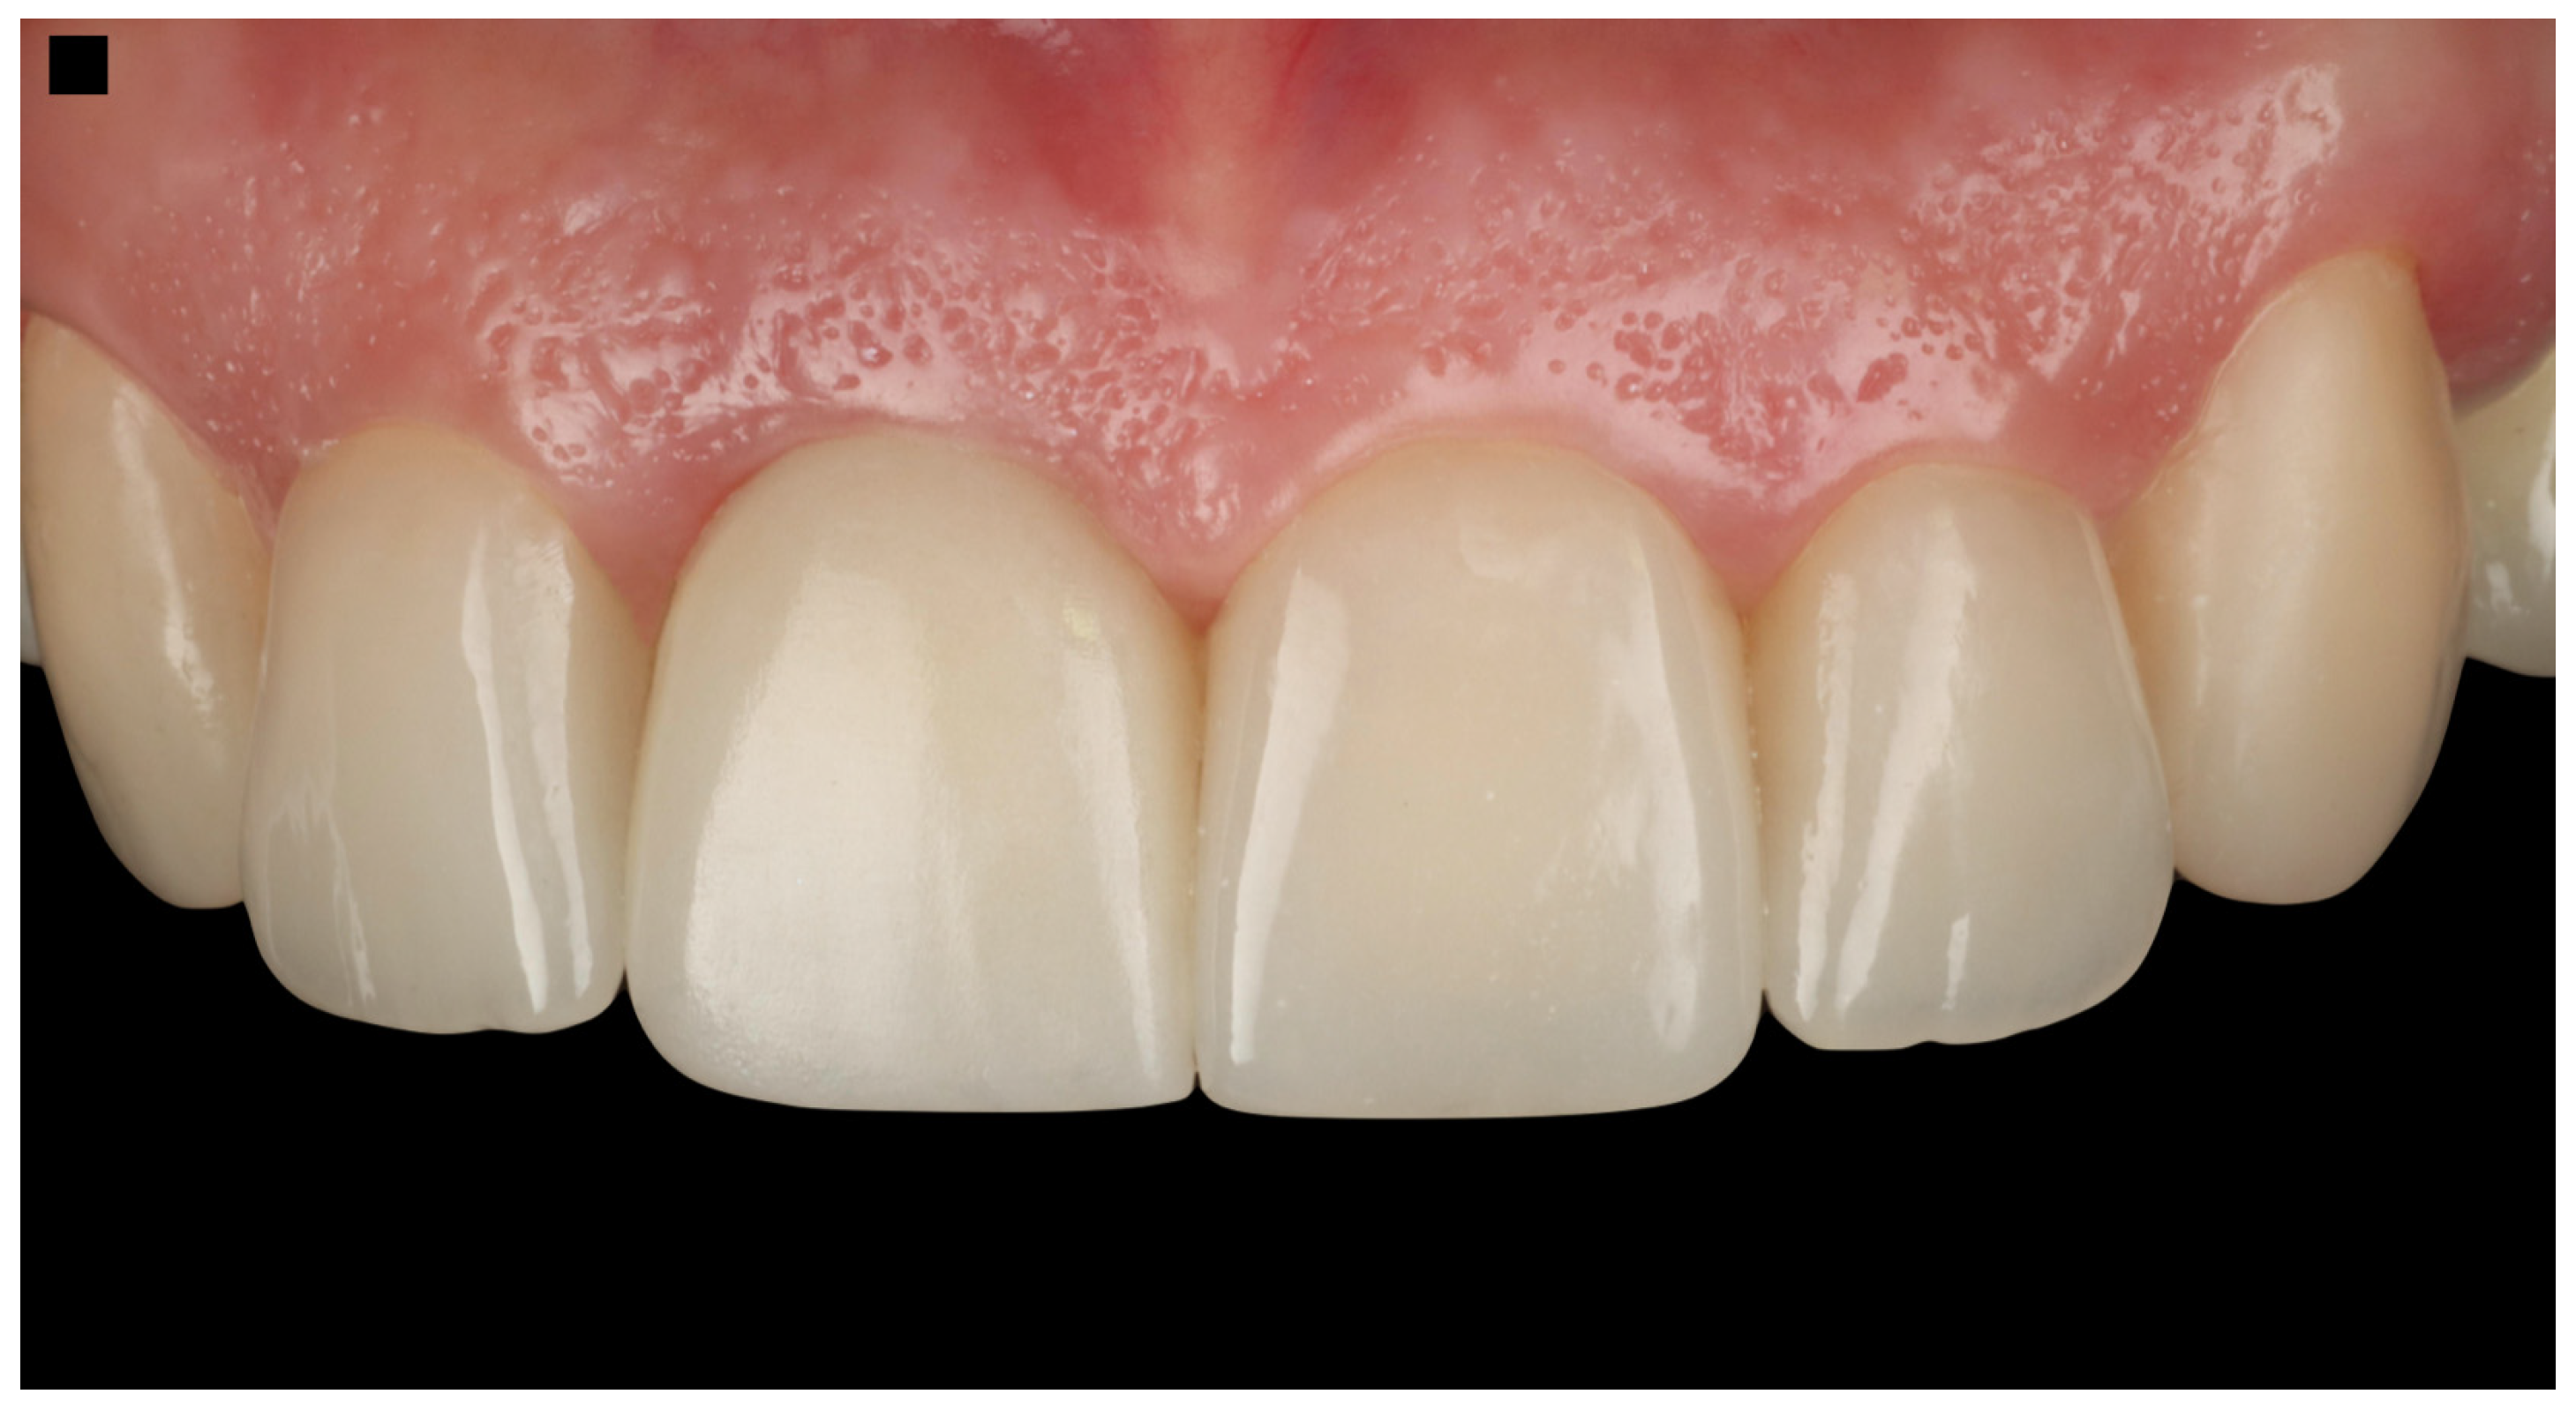

Figure 10.

Final restorations.

The patient expressed complete satisfaction with the final restorations, praising the natural shade and shape of the teeth. To protect the restorations from potential damage, the patient was provided with a custom-made night guard. Detailed oral hygiene instructions were given, emphasizing the importance of maintaining the health of the restorations and surrounding tissues. The patient was scheduled for regular follow-up visits every six months for professional dental prophylaxis and to monitor the condition of the restorations and periodontal tissues (Figure 10). At the three-year follow-up visit, the patient was still satisfied with the outcome.

The Pink Esthetic Score (PES) is a system used to evaluate the esthetic outcomes of soft tissues surrounding dental implants, particularly in the anterior region of the mouth. It is a well-accepted method in the literature for assessing treatment success [47]. The PES evaluates five variables: mesial and distal papilla, curvature of the gingival margin, level of the gingival margin, root convexity, and scar formation. Each variable is scored on a 0–1–2 scale, where 2 represents the best outcome and 0 the poorest. The maximum score is 14, with scores of 11 or above generally considered excellent, scores between 8 and 11 deemed acceptable, and scores below 8 considered poor. Based on the PES system, the results of the case presented in this study provide a score of 12, which is considered an excellent result (Figure 11).